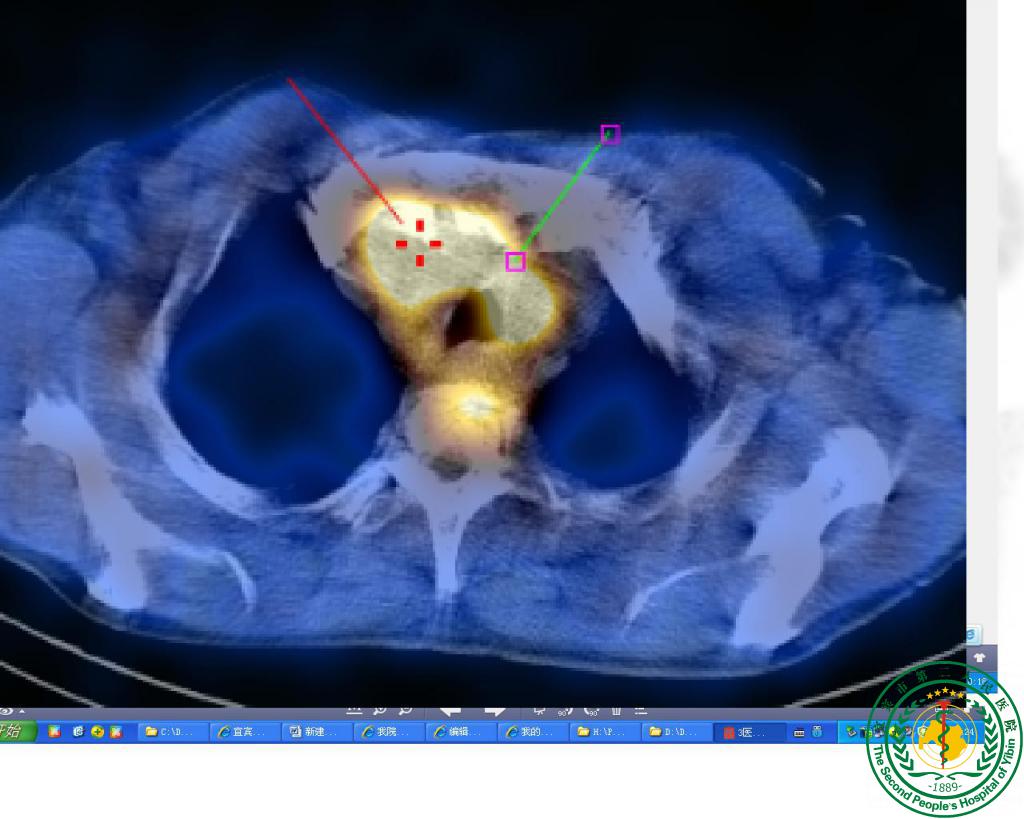

“鹰眼”派特CT确诊疑难“肺结节”一例

“鹰眼”派特CT确诊疑难“肺结节”一例6248

宜宾市第二人民医院 图文